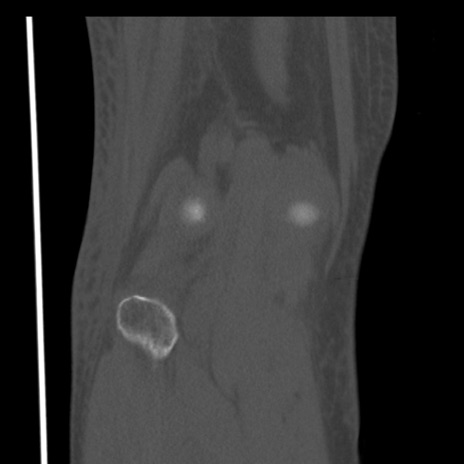

右膝関節CT

横断像